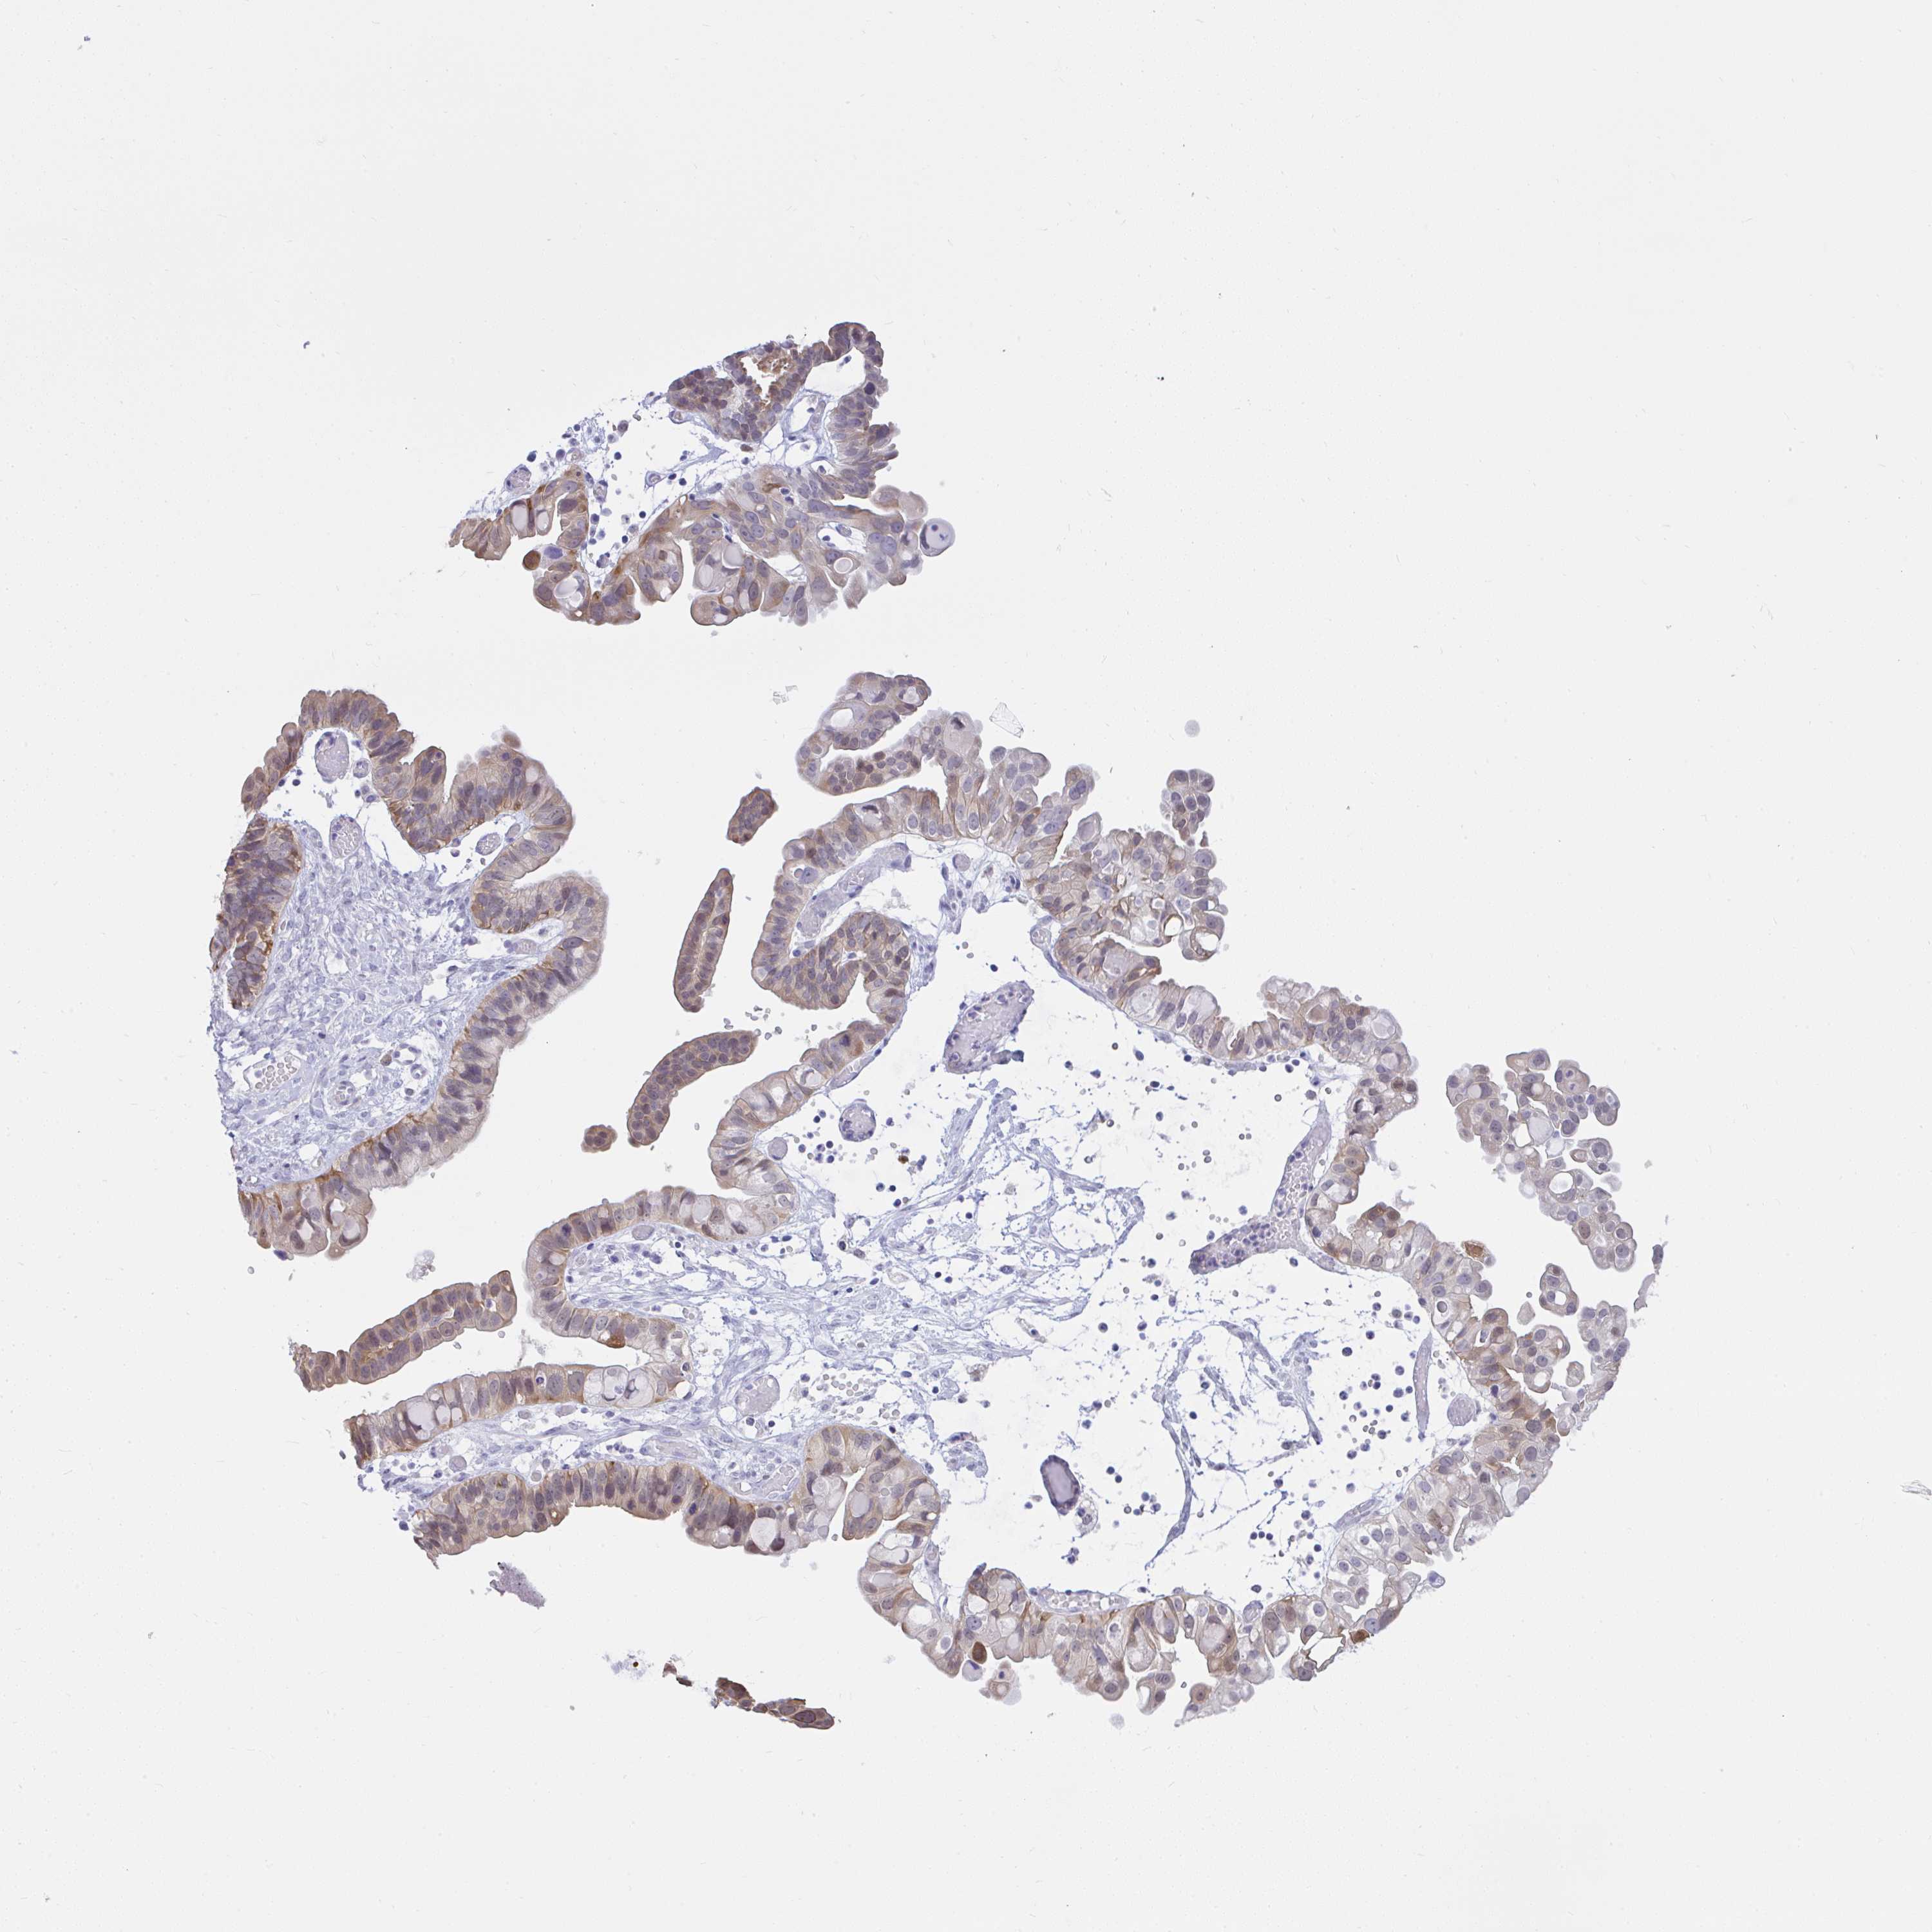

OVARIAN CANCER - Protein expressioni

A mouse-over function shows sample information and annotation data. Click on an image to view it in a full screen mode. Samples can be filtered based on level of antibody staining by selecting one or several of the following categories: high, medium, low and not detected. The assay and annotation is described here.

Note that samples used for immunohistochemistry by the Human Protein Atlas do not correspond to samples in the TCGA dataset.

Antibody stainingi

Antibody staining in the annotated cell types in the current human tissue is reported as not detected, low, medium, or high, based on conventional immunohistochemistry profiling in selected tissues. This score is based on the combination of the staining intensity and fraction of stained cells.

Each image is clickable and will lead to virtual microscopy that enables deeper exploration of all samples and also displays staining intensity scores, fraction scores and subcellular localization as well as patient and tissue information for each sample.

Antibody HPA059356

Staining

High

Medium

Low

Not detected

Intensity

Strong

Moderate

Weak

Negative

Quantity

>75%

75%-25%

<25%

None

Location

Nuclear

Cytoplasmic/membranous

Cytoplasmic/membranous,nuclear

Cystadenocarcinoma, serous, NOS

Carcinoma, endometroid

Cystadenocarcinoma, mucinous, NOS

Carcinoma, NOS